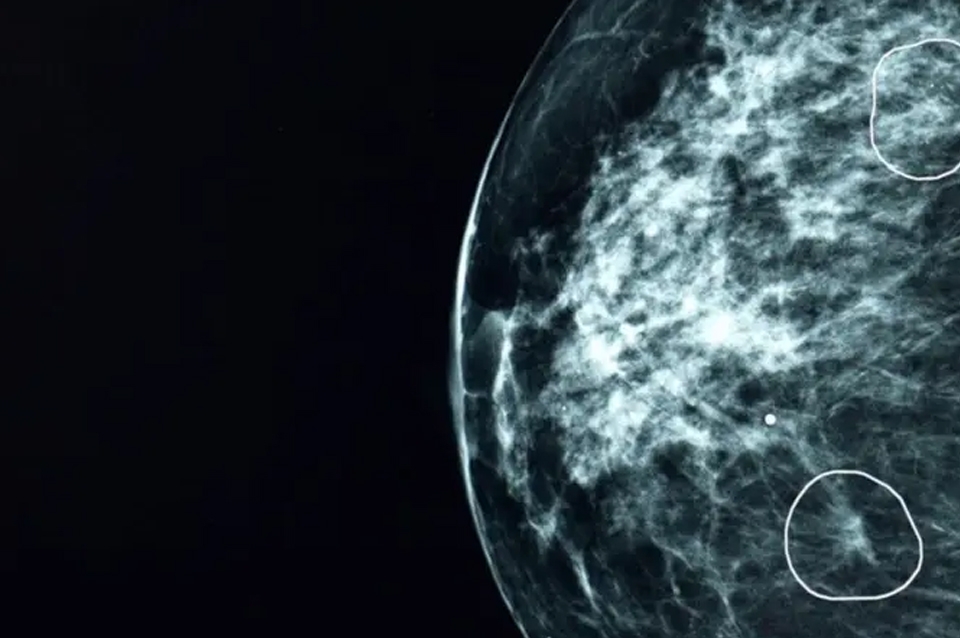

La BBC pudo ver la herramienta en acción en el hospital Grampian, presenciando cómo unos tumores prácticamente invisibles al ojo humano eran señalados por la herramienta.

En sus etapas iniciales, los cánceres pueden ser extremadamente pequeños y difíciles de identificar.

Gracias a esto, su tumor -de apenas 6 mm- fue detectado de forma temprana, por lo que solo necesitó una operación y seis días de radioterapia.